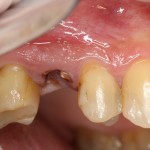

Чем хороша немедленная имплантация?

т. е., установка импланта в лунку только что удаленного зуба?

Да тем, что это позволяет получить хороший результат с минимальными временными, финансовыми и прочими трудозатратами! На фотографиях выше — зуб моего коллеги несколько месяцев назад. Был штифт, была коронка, всё это дело благополучно развалилось в течение нескольких лет. Врач-ортопед сказал, что реставрировать такую культю невозможно, рекомендовал удаление.